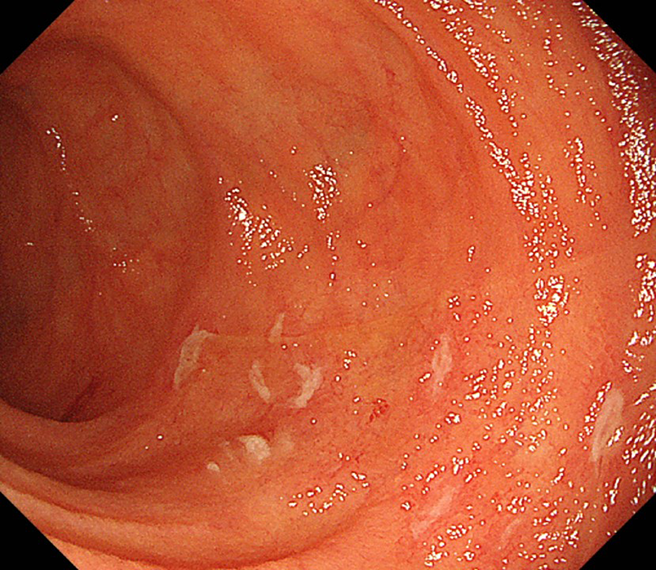

バルーン内視鏡検査における小腸病変

回腸に縦走配列するアフタ様潰瘍を認める。